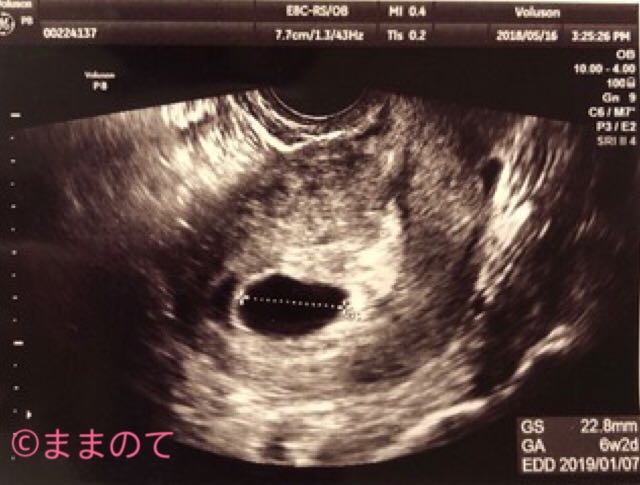

妊娠6週の赤ちゃんのエコー画像

妊娠6週の健診では経腟の超音波検査が行われます。上のエコー画像は妊娠6週2日の子宮の断面を写したもので、真ん中の黒い丸は胎嚢です。

このエコー画像には胎嚢しか写っていませんが、妊娠6週の超音波検査では胎嚢の中に卵黄嚢(赤ちゃんの栄養源)や胎芽が見えることがあります。卵黄嚢はリング状、胎芽はあずきのような丸い形で胎嚢の中に白く写し出されますよ。